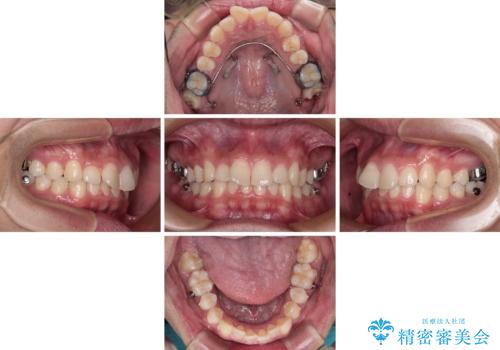

インビザラインによる矯正治療をご希望でしたが、上顎歯列の前方位と鋏状咬合を確実に改善することを目的として、補助装置を併用することとしました。

補助装置を併用せずに治療を終える可能性はありましたが、確実に結果を得るために補助装置を活用しました。